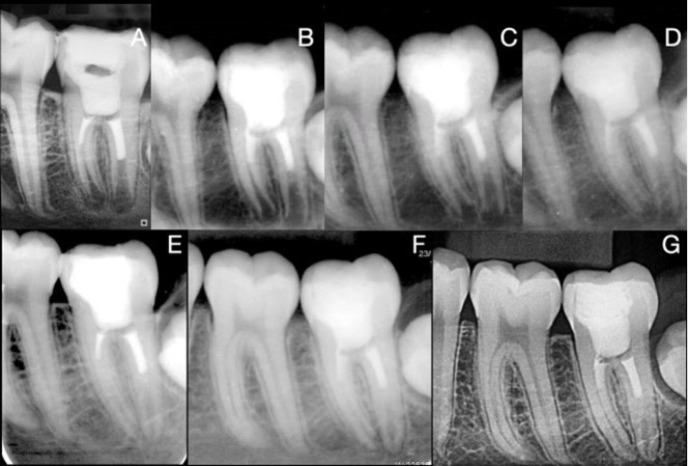

Vital pulp therapy is one of the least invasive and simplest and most economically acceptable treatment alternatives for immature teeth with pulpitis. The success rate of this treatment, with calcium silicate-based cements, ranges from 85% to 100%. Vital pulp therapy prevents the development of apical periodontitis and promotes normal root development, allowing the tooth to remain in the dentition and perform its functions. The patient was a nine-year-old boy with pain on chewing and a positive response to cold. The panoramic radiograph showed an immature permanent lower molar with deep caries. Partial pulpectomy and root pulp sealing with pre-mixed calcium silicate-based cement were performed under aseptic conditions. The absence of symptoms and the formation of roots with apical sealing were successfully achieved and observed by follow-up and radiographic control, making this treatment a viable option for immature teeth with pulpitis.